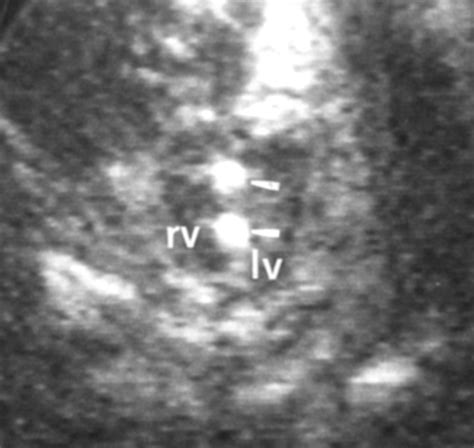

• Intracardiac Echogenic Foci: Often found in the heart, these are common and frequently benign. While they have sometimes been associated with an increased risk of chromosomal abnormalities (like Down syndrome), in low-risk pregnancies with no other markers, they are often considered a normal variation of development.

Intracardiac Often benign; sometimes a soft marker for chromosomal conditions.